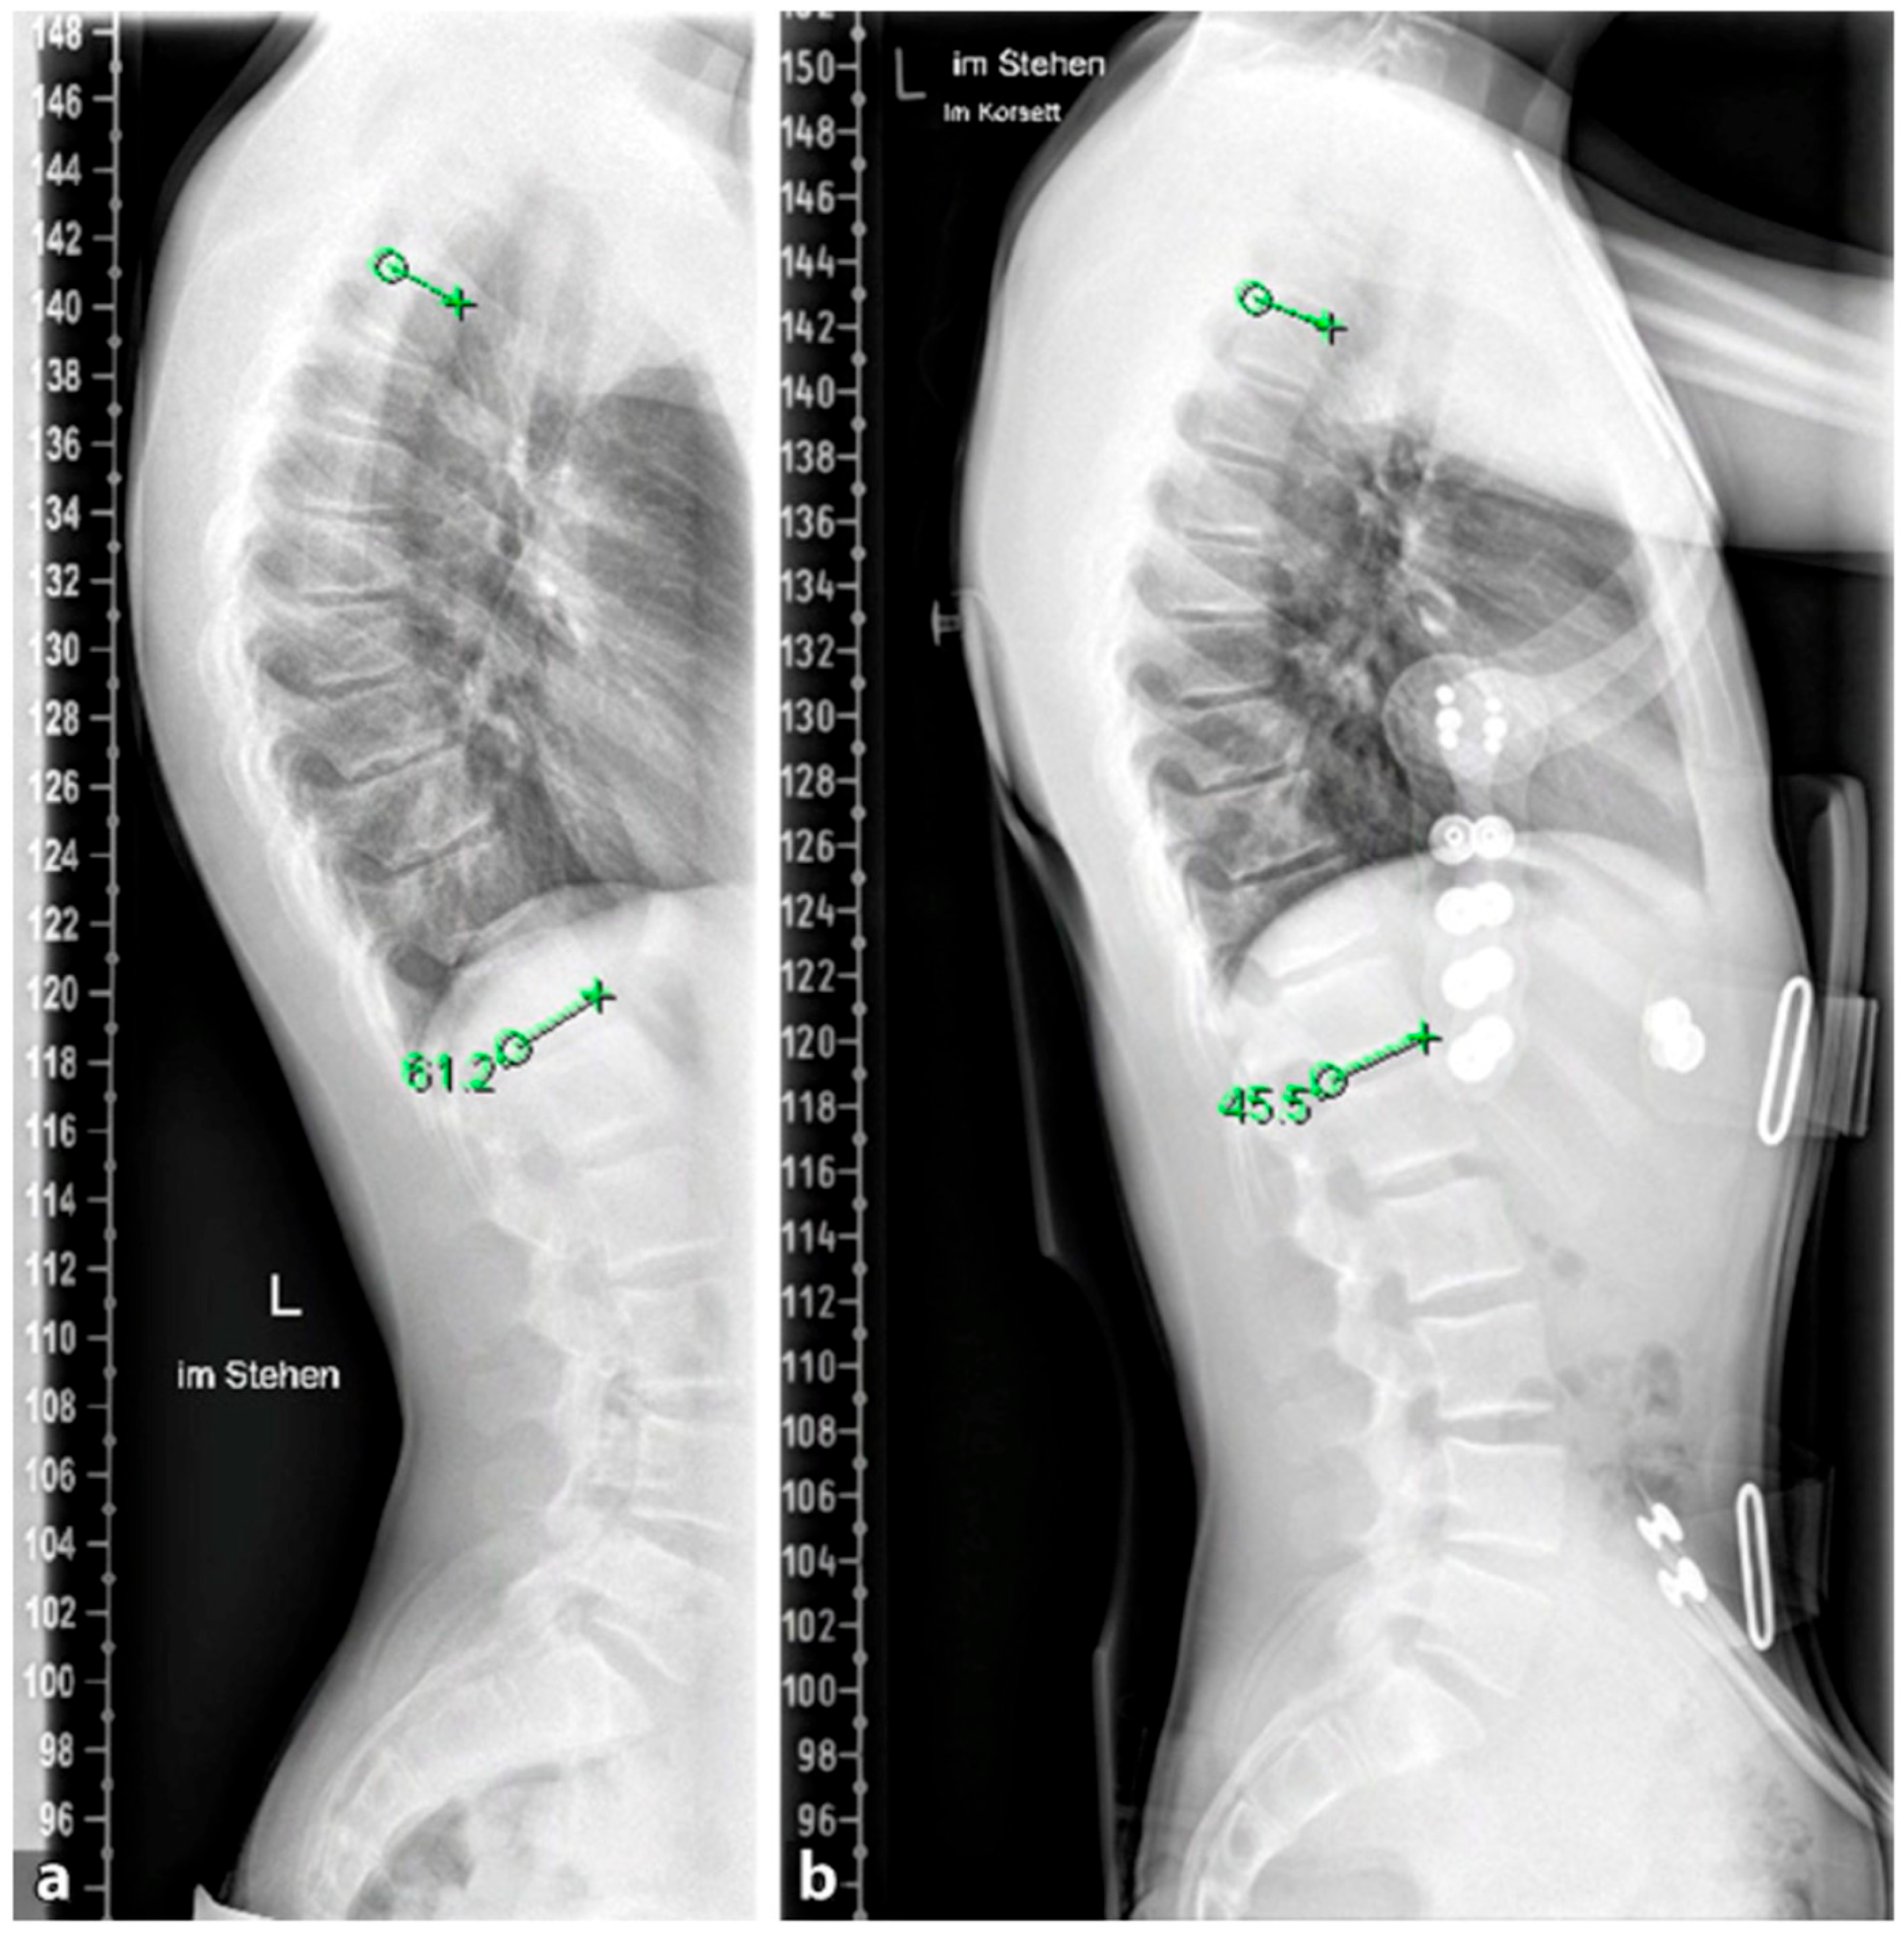

Figure 5. (a,b). Initial radiographs of a patient with adolescent idiopathic scoliosis. (c,d). Bending radiographs. (e,f). Postoperative image displaying implanted magnetically controlled growing rods as a dual rod system. (g,h). The patient was treated with a spondylodesis upon the completion of growth to maintain correction success (Reprinted with permission [10]).